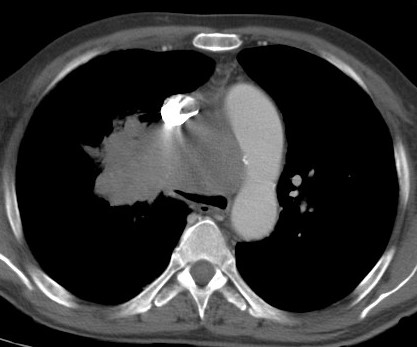

¿Qué es el Cáncer de pulmón?

Es uno de los cánceres mas agresivos y mas frecuentes en hombres y mujeres. En el 90% de los casos ocurre en fumadores de larga evolución. Existen diferentes tipos de tumores que se tratan de forma diferente según el tipo de células que predominan en la lesión. Los síntomas de alerta que deben llevar a […]